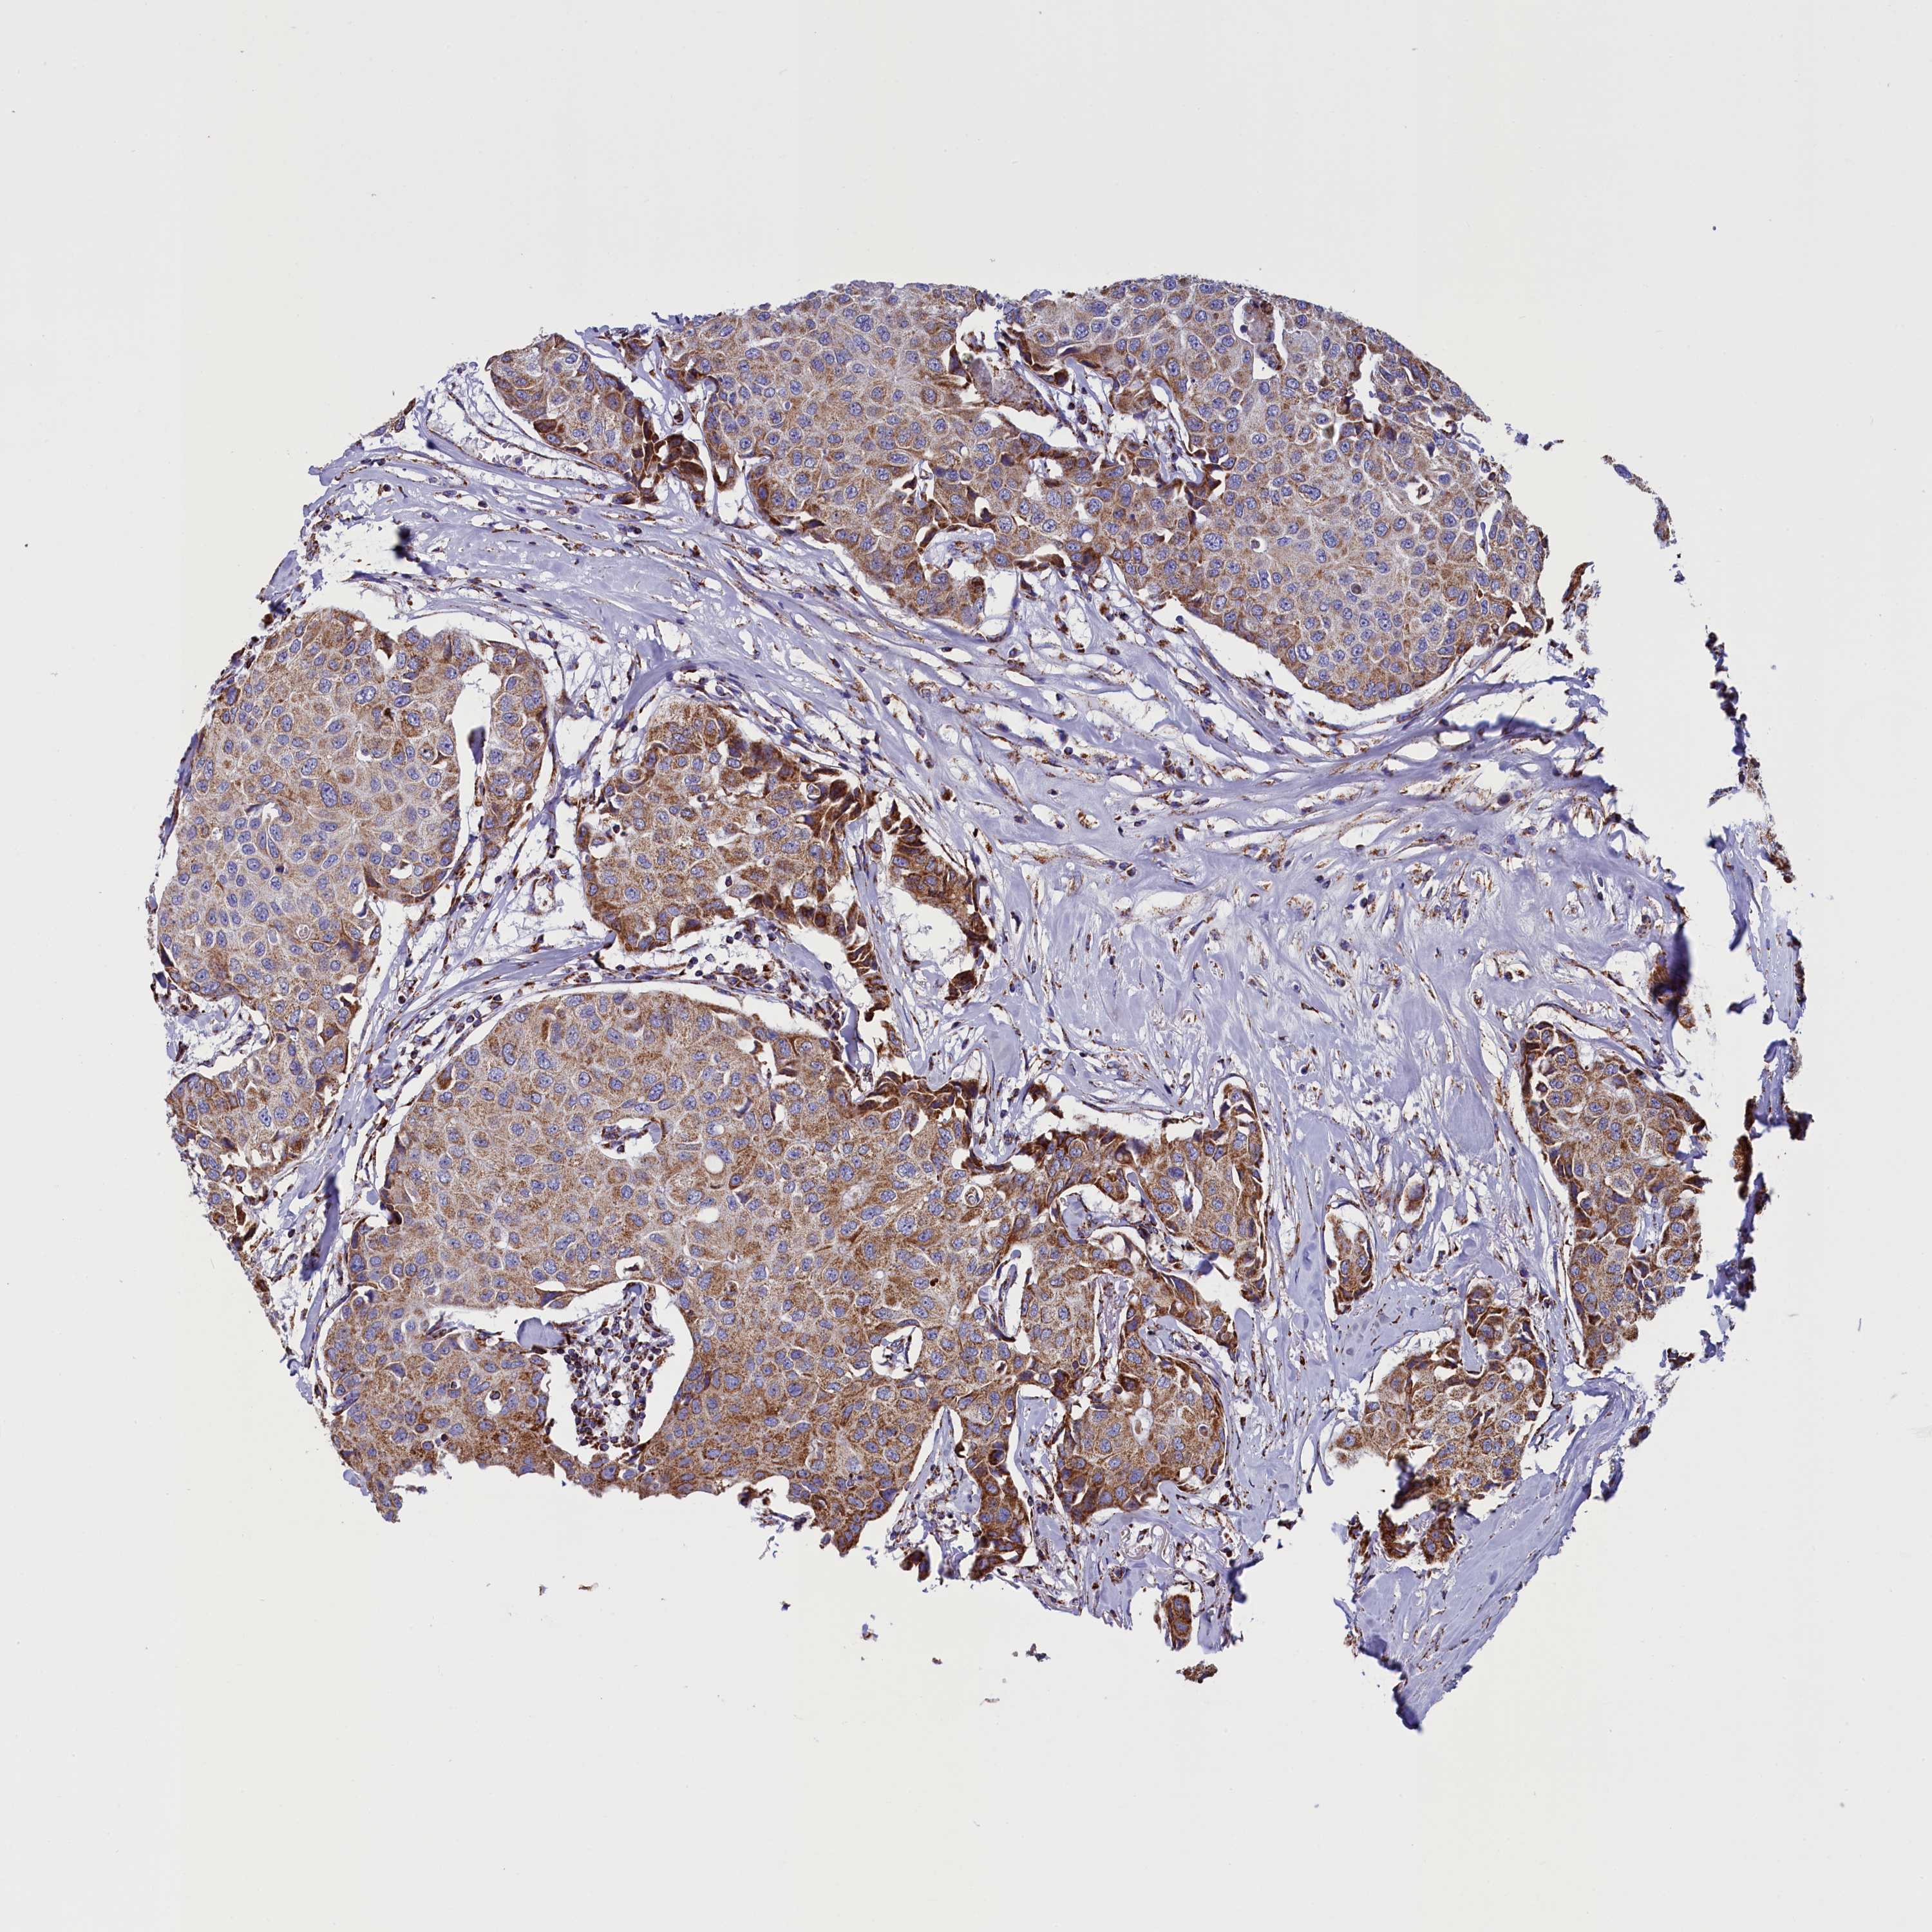

CANCER BREAST CANCER Show tissue menu

BRCA TCGA BRCA VALIDATION PROTEIN EXPRESSION